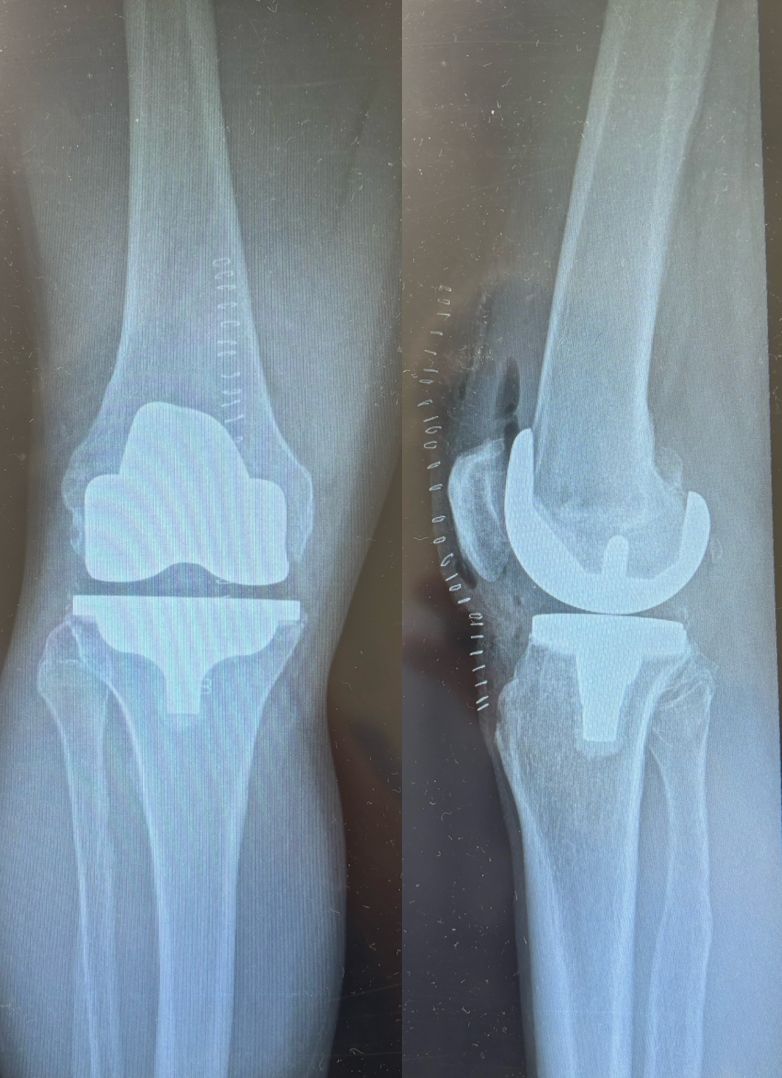

Ho maturato una solida esperienza nella chirurgia protesica mini-invasiva di anca e ginocchio. Eseguo interventi di protesi di anca mediante accesso anteriore “bikini” e accesso posterolaterale, interventi di protesi di ginocchio sia monocompartimentale che totale. Tratto la traumatologia sportiva di ginocchio e spalla mediante l’utilizzo di tecniche artroscopiche mini-invasive.